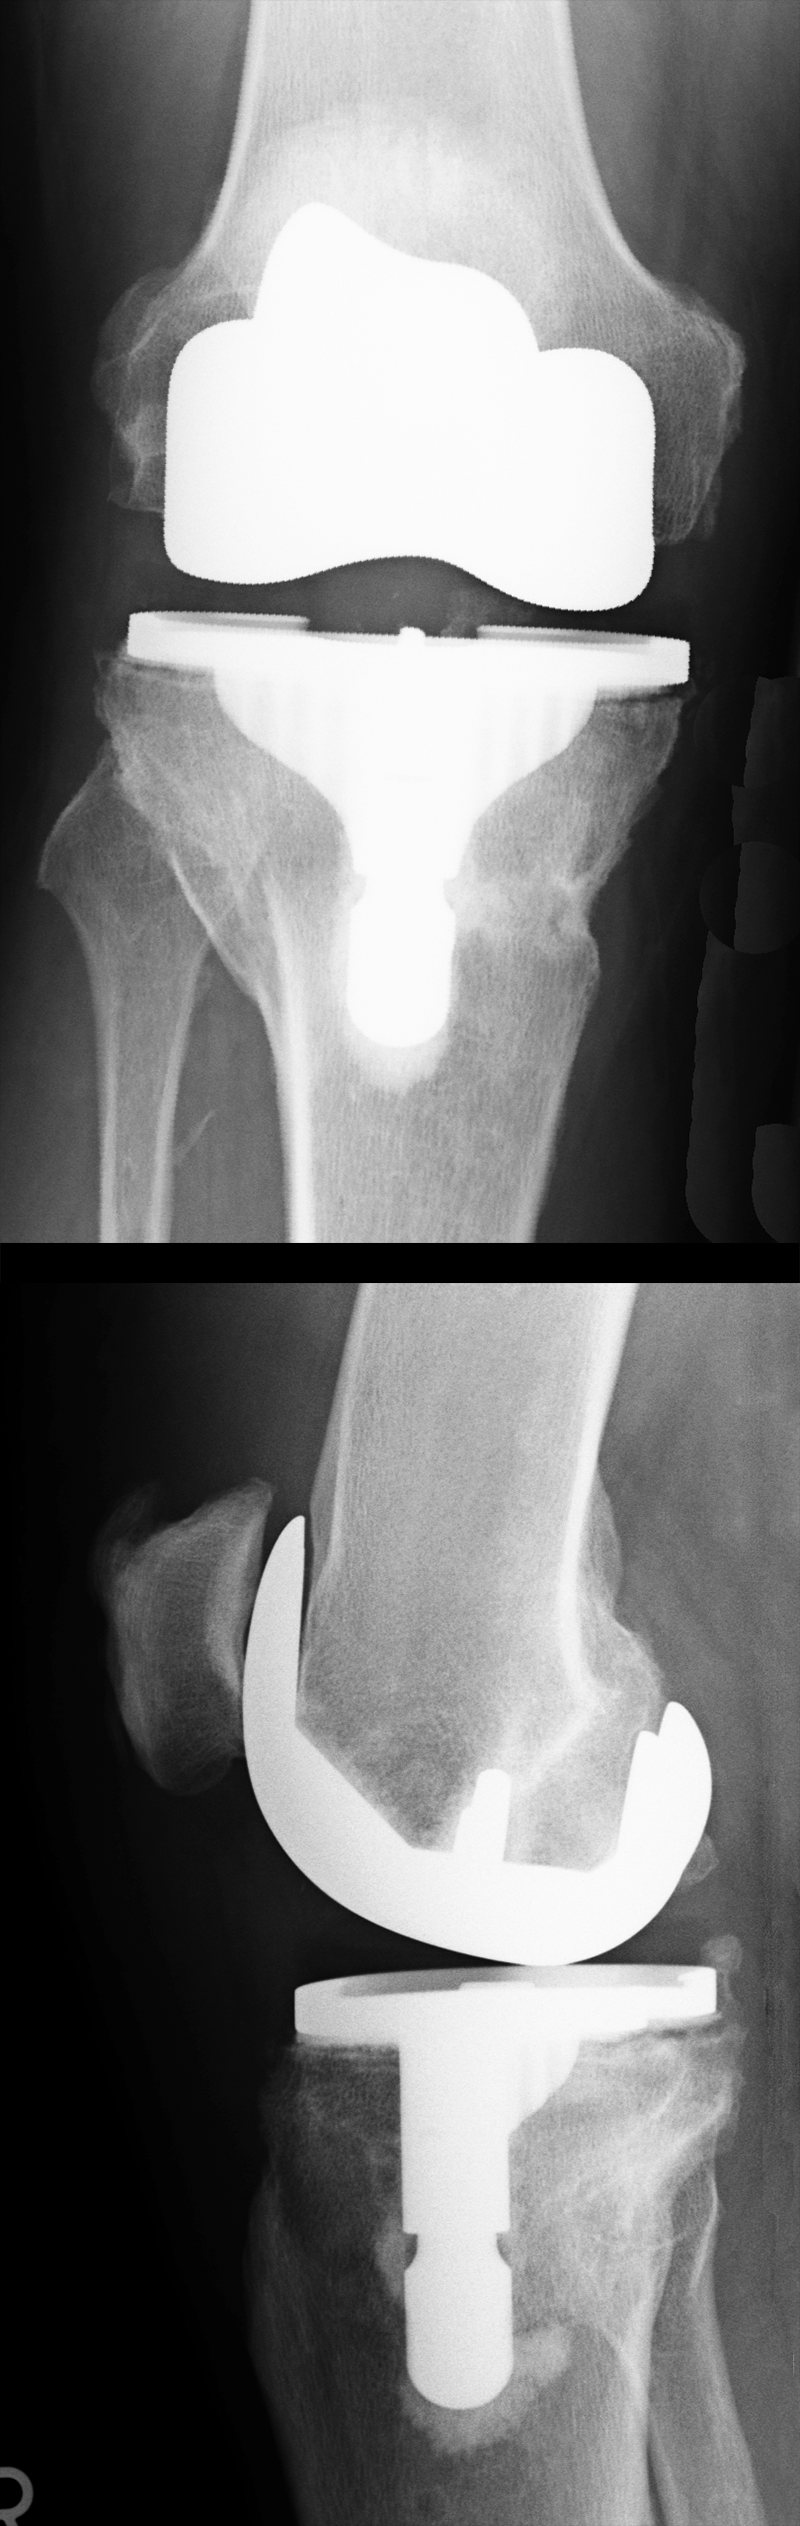

Dem aufmerksamen Beobachter fällt vielleicht auf, dass die Knochenstruktur im Schienbeinkopf im Schaftbereich der Prothese irgendwie merkwürdig ist. Das liegt daran, dass hier der Implantation der Endoprothese eine Umstellungsosteotomie vorausgegangen ist.